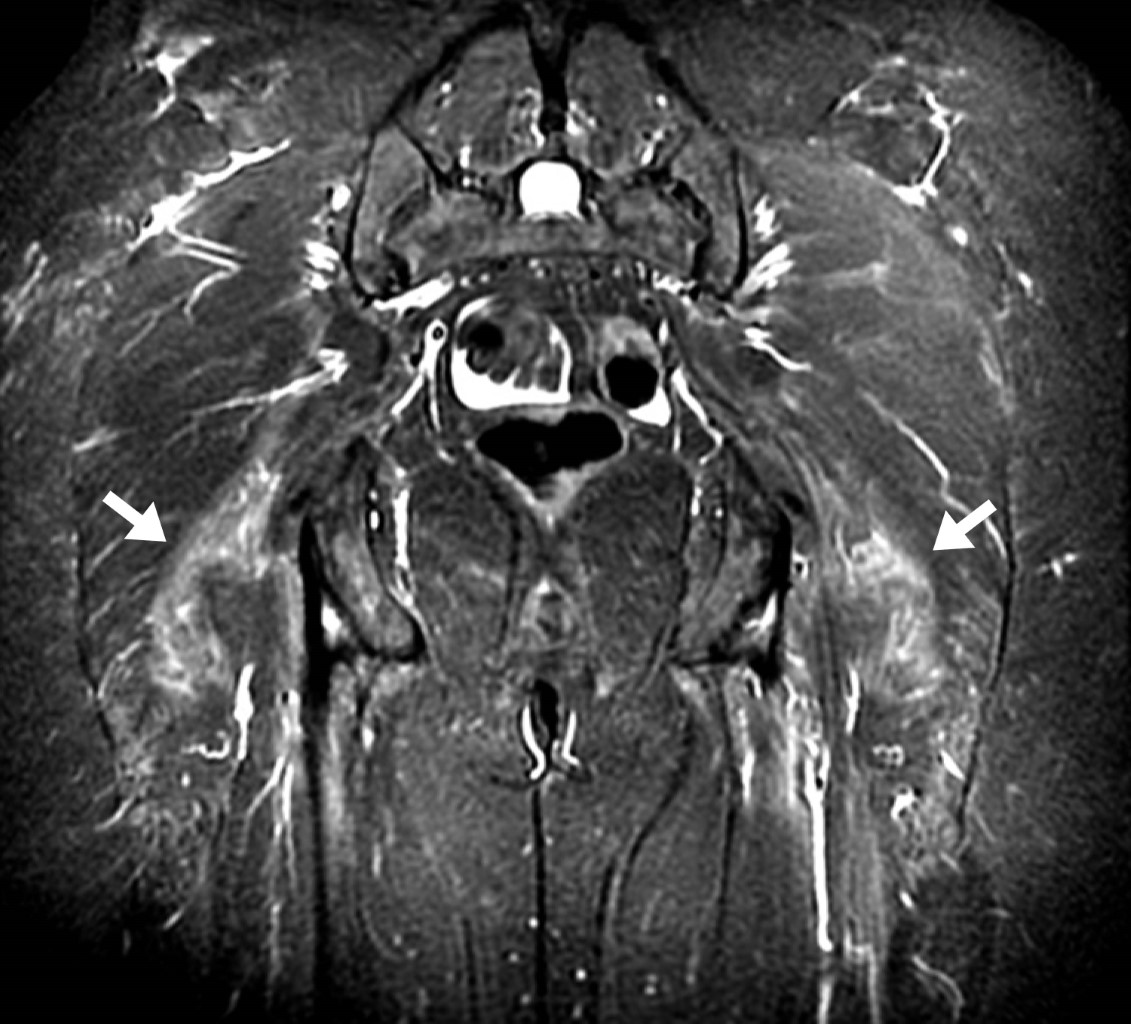

Mujer de 56 años, peso 58 kg, estatura 1.54 m, a quien se le solicitó resonancia magnética del nervio ciático por presentar síntomas de dolor en la pierna izquierda de dos meses de evolución, en estudio previo de resonancia magnética de columna lumbar no se demostró patología discal. En el estudio se identificó asimetría de los músculos piriformes, en las imágenes axiales del lado izquierdo el músculo piriforme mide hasta 12.7 mm de grosor y en el lado derecho 6 mm (Figura 1), en imágenes coronales mide en el lado derecho 8.4 mm y en el lado izquierdo hasta 16 mm (Figura 2), con incremento de la señal del músculo piriforme en el lado izquierdo y datos de compresión del nervio ciático a este nivel. Como otros hallazgos, la paciente presentó cambios de coxartrosis incipiente, bursitis trocantérica bilateral y edema leve por proceso inflamatorio bilateral de los músculos glúteo mayor y medio (Figura 3).

Figura 2